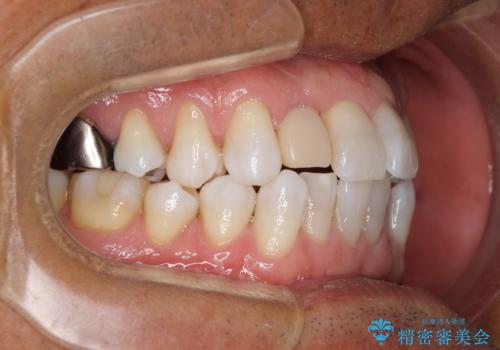

治療途中の前歯を治したい インビザライン矯正とオールセラミッククラウン

- 治療途中の前歯と上下前歯のデコボコ気にして来院された患者様です。

前歯のデコボコはインビザラインにより歯列を整え、その後に、前歯などをオーダーメイドタイプのオールセラミッククラウンにて補綴治療することとしました。

長時間のマウスピース装着に協力いただき、短期間で歯列をしっかりと改善することができました。

ホームホワイトニングを併用していただいたので、とても明るい口元に仕上がり、患者様には大変満足していただきました。